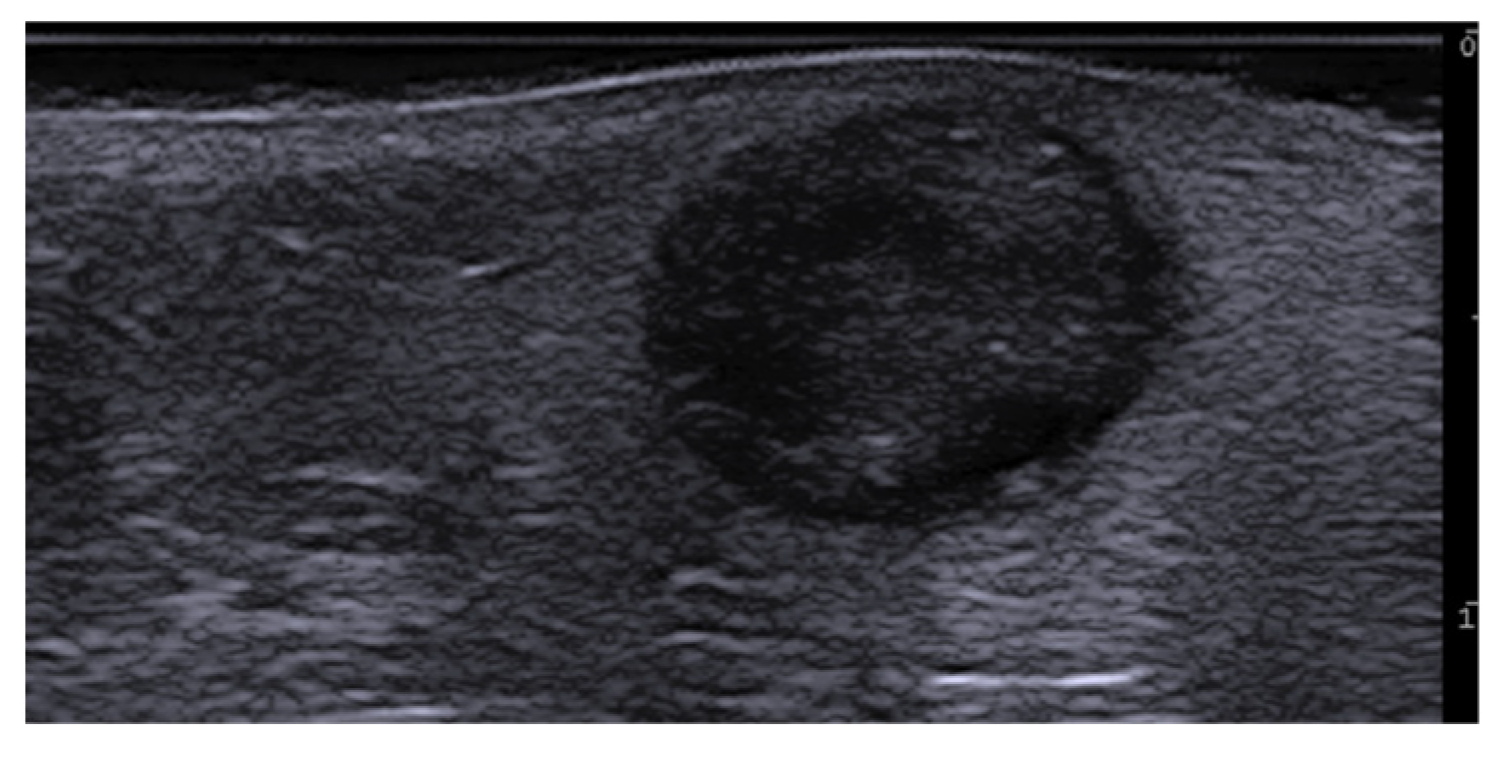

7. External-Agent-Associated Disorders

8. Neoplastic Diseases